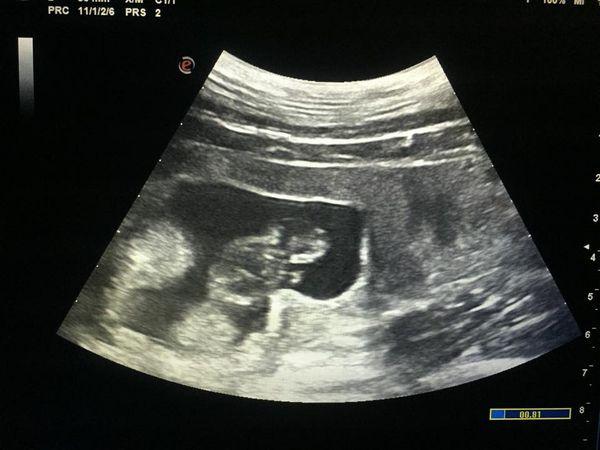

盈盈早於2015年被確認懷有體長3.5厘米的胎兒。(@FB香港海洋公園 Ocean Park Hong Kong圖片)

2015年超聲波檢查發現流產

然而,在公布有喜不足一星期,海洋公園再為牠照超聲波檢查,就發現體內的胎兒已停止發育,更有部份結構已被盈盈體內吸收,相信盈盈不幸流產;海洋公園獸醫稱,料流產對盈盈健康影響不大。